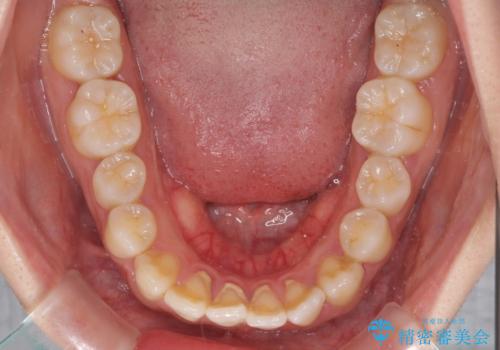

軽微な歯列不正をワイヤー矯正で整える

- 上顎歯列と下顎前歯の叢生を気にして来院された患者様です。

上顎からワイヤー矯正を開始し、終了間際から下顎前歯の叢生解消するよう計画しました。

部分矯正でしたが、咬み合わせに違和感が出ることなく気になる部分を改善させることができました。